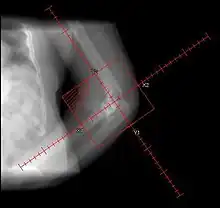

| Heterotopic ossification around the hip joint in a patient who has undergone hip arthroplasty |